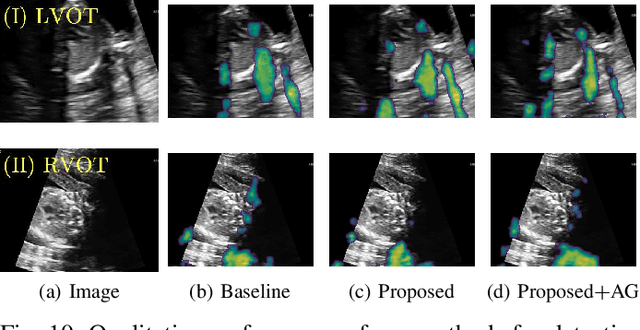

Abstract:Detecting acoustic shadows in ultrasound images is important in many clinical and engineering applications. Real-time feedback of acoustic shadows can guide sonographers to a standardized diagnostic viewing plane with minimal artifacts and can provide additional information for other automatic image analysis algorithms. However, automatically detecting shadow regions is challenging because pixel-wise annotation of acoustic shadows is subjective and time consuming. In this paper we propose a weakly supervised method for automatic confidence estimation of acoustic shadow regions, which is able to generate a dense shadow-focused confidence map. During training, a multi-task module for shadow segmentation is built to learn general shadow features according based image-level annotations as well as a small number of coarse pixel-wise shadow annotations. A transfer function is then established to extend the binary shadow segmentation to a reference confidence map. In addition, a confidence estimation network is proposed to learn the mapping between input images and the reference confidence maps. This confidence estimation network is able to predict shadow confidence maps directly from input images during inference. We evaluate DICE, soft DICE, recall, precision, mean squared error and inter-class correlation to verify the effectiveness of our method. Our method outperforms the state-of-the-art qualitatively and quantitatively. We further demonstrate the applicability of our method by integrating shadow confidence maps into tasks such as ultrasound image classification, multi-view image fusion and automated biometric measurements.